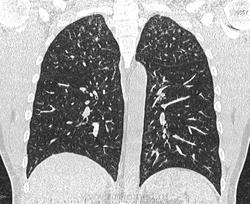

По jpeg впечатление очаговых изменений верхних долей и умеренного увеличения лимфоузлов средостения. Туберкулез на первое место.

Моё мнение то же самое, туберкулез. Добавила изображения.

Посев мокроты на туберкулез отрицательный. Пульмонолог по КТ ставит саркоидоз легких 2 степени. Какое Ваше мнение?

В диф. ряд на первое место предполагаю все же саркоидоз легких и ВГЛУ (по одной из классификаций 2 стадия, а не степень). В плане дальнейшего диагностического алгоритма: